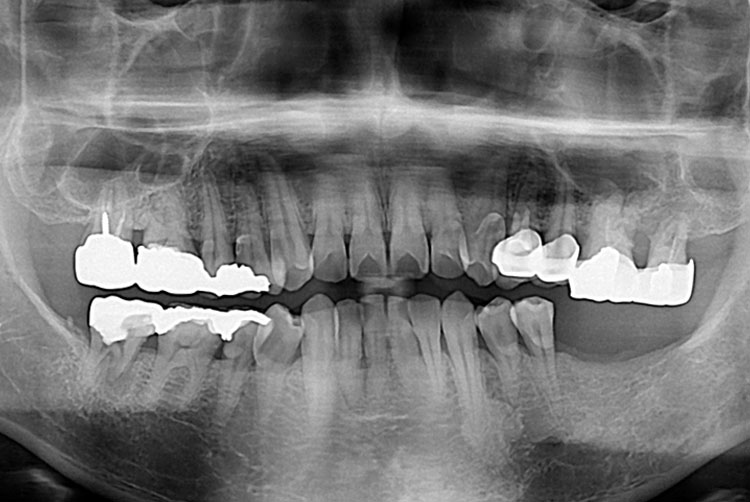

치료전 : 2016-08-18

박성우_후.jpg

치료후 : 2006-09-29

세종치과는 많은 환자와 다양한 케이스를 바탕으로 항상 편안한 임플란트 수술을 제공하고자 노력하고,

오래동안 튼튼히 쓸 수 있는 임플란트 수술을 가장 큰 목표로 삼고 있습니다.